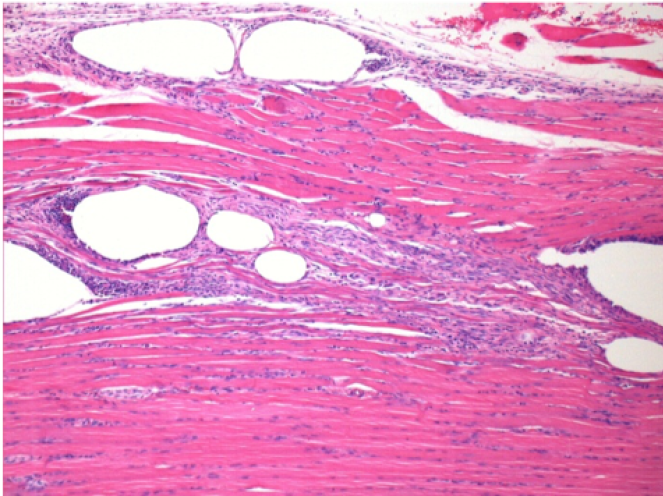

بعد 10 أيام من حقن إندوبيل

10 أيام بعد حقن إندوبيل 0.1 مل في العضلة أمام الظنبوب الأيمن.

هنا قد ترى تشكيل الفجوات التي تحيط بها الخلايا اللمفاوية. الفجوات تختلف عن نخر الأنسجة. يرتبط وجود الخلايا اللمفاوية بنفاذية أغشية الخلايا.

L : Control-100xD10

R:100xD10

R :200xD10

R :400xD10